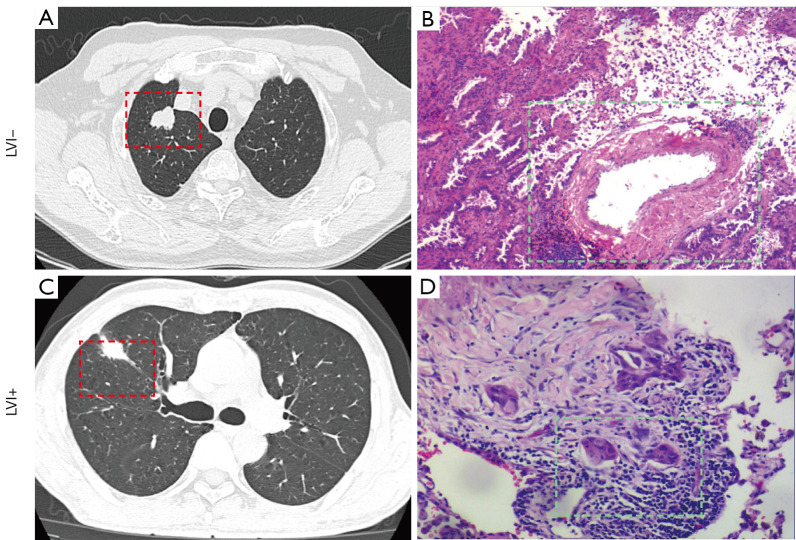

Background: Lymphovascular invasion (LVI) is a high-risk pathological marker for the evaluation of metastasis and prognosis of non-small cell lung cancer (NSCLC). Preoperative computed tomography (CT) prediction of vascular invasion in NSCLC is essential for clinical identification of high-risk patients and development of treatment strategies. This study aimed to develop and validate a model for predicting LVI in NSCLC based on clinical and CT features.

Results: A total of 2,830 patients with NSCLC were included, including 1,190 (42.1%) males and 1,640 (57.9%) females, with a mean age of 61.15±10.83 years. Independent risk factors for LVI of NSCLC included the history of smoking, the history of diabetes mellitus, laboratory tumor indices, mixed ground-glass nodule (mGGN) consolidation/tumor ratio (CTR), and vacuole signs. The area under the curve (AUC), accuracy, sensitivity, and specificity for the training set were 0.836 [95% confidence interval (CI): 0.806-0.867], 65.2%, 92.1%, and 63.5%; those for the validation set were 0.803 (95% CI: 0.755-0.852), 71.6%, 82.7%, and 70.9%; and those for the external validation set were 0.845 (95% CI: 0.775-0.916), 70.9%, 87.8%, and 68.6%, respectively.

Conclusions: We developed and validated a model for predicting LVI in NSCLC based on clinical and CT image features. The model developed in this study has potential application value in predicting LVI in NSCLC. It provides a new, operable, and non-invasive technique for clinical identification of high-risk patients and may help clinical selection of appropriate treatment.